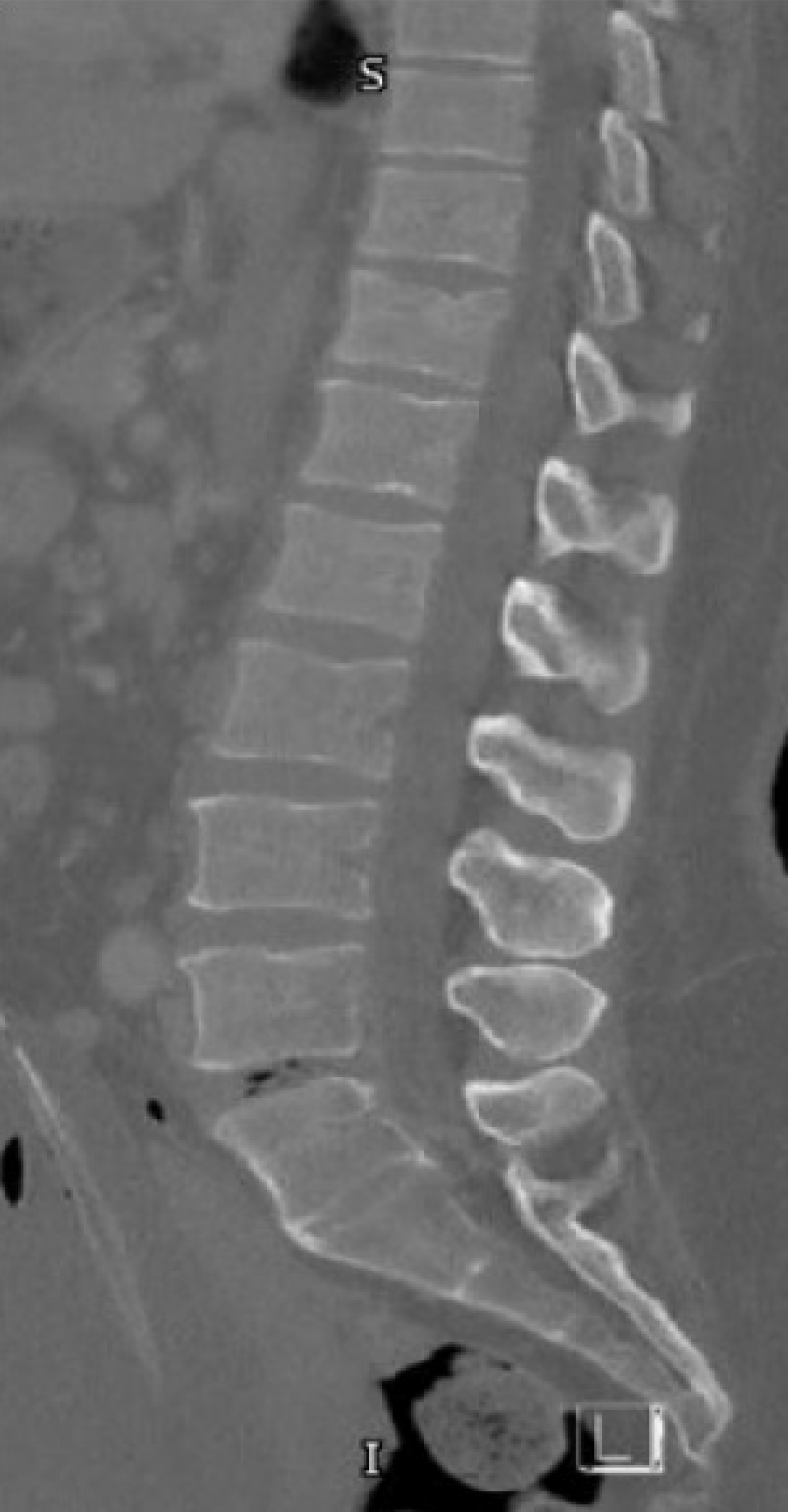

Case 4: The e-FAST was negative, and both chest and pelvic X-rays were normal. Pan-CT scan revealed a C4 spinous process fracture, an anterior compression fracture of the vertebral body, and a fracture of the left superior articular process of the 7th thoracic vertebra (T7). MRI of the spine confirmed these findings and additionally showed interspinous and supraspinous ligament injuries at C3-C4 and C4-C5, intervertebral disc protrusion at C6-C7, causing spinal canal narrowing and abutting the cervical cord without significant compression, anterior wedging and mild compression with retropulsion of T7, and a compression fracture of T8.

Case 5: e-FAST was negative, and a pan-CT revealed a T12 vertebral fracture. Additional injuries included an epidural hematoma in the basal cisterns, pituitary fossa, and parasellar areas, ethmoid sinus fracture, nasal bone fracture, right lung contusions, and fractures of the left acetabulum and iliac bone.

He was managed conservatively with a thoracolumbar brace and was successfully discharged after five days. This injury pattern reflects a combined flexion-compression mechanism with associated ligamentous failure. The C4 spinous process fracture and cervical interspinous/supraspinous ligament injury suggest a flexion-distraction component, while the disc protrusion at C6-C7 is likely due to shear forces during flexion. The T7 anterior compression with retropulsion and the T8 compression fracture are consistent with axial compressive loading, resulting in a wedge deformity of the thoracic spine. The combination of bony fractures and posterior ligamentous disruption highlights the mixed forces sustained during the rollover.

She received conservative management for the T12 fracture and other injuries and underwent surgical fixation for her pelvic fracture. Her GCS improved; she was extubated and later transferred to the ward, where she was discharged after 5 days. The thoracolumbar junction marks the transition between the rigid thoracic and flexible lumbar spine, making it vulnerable to injury. The T12 vertebral body fracture resulted from axial compression. The rollover accident caused vertical loading and flexion forces, leading to a wedge-shaped T12 fracture. Associated craniofacial injuries suggest a high-energy deceleration mechanism, while the pelvic ring fracture reflects secondary axial load transmission during ejection and ground impact.

Three patients in our series sustained thoracic spine injuries. One had T7 anterior wedging, mild compression with retropulsion, and a T8 compression fracture. Another had a T12 anterior superior endplate fracture (Figure 4). The third patient had a fracture of the anterosuperior endplates of T4.